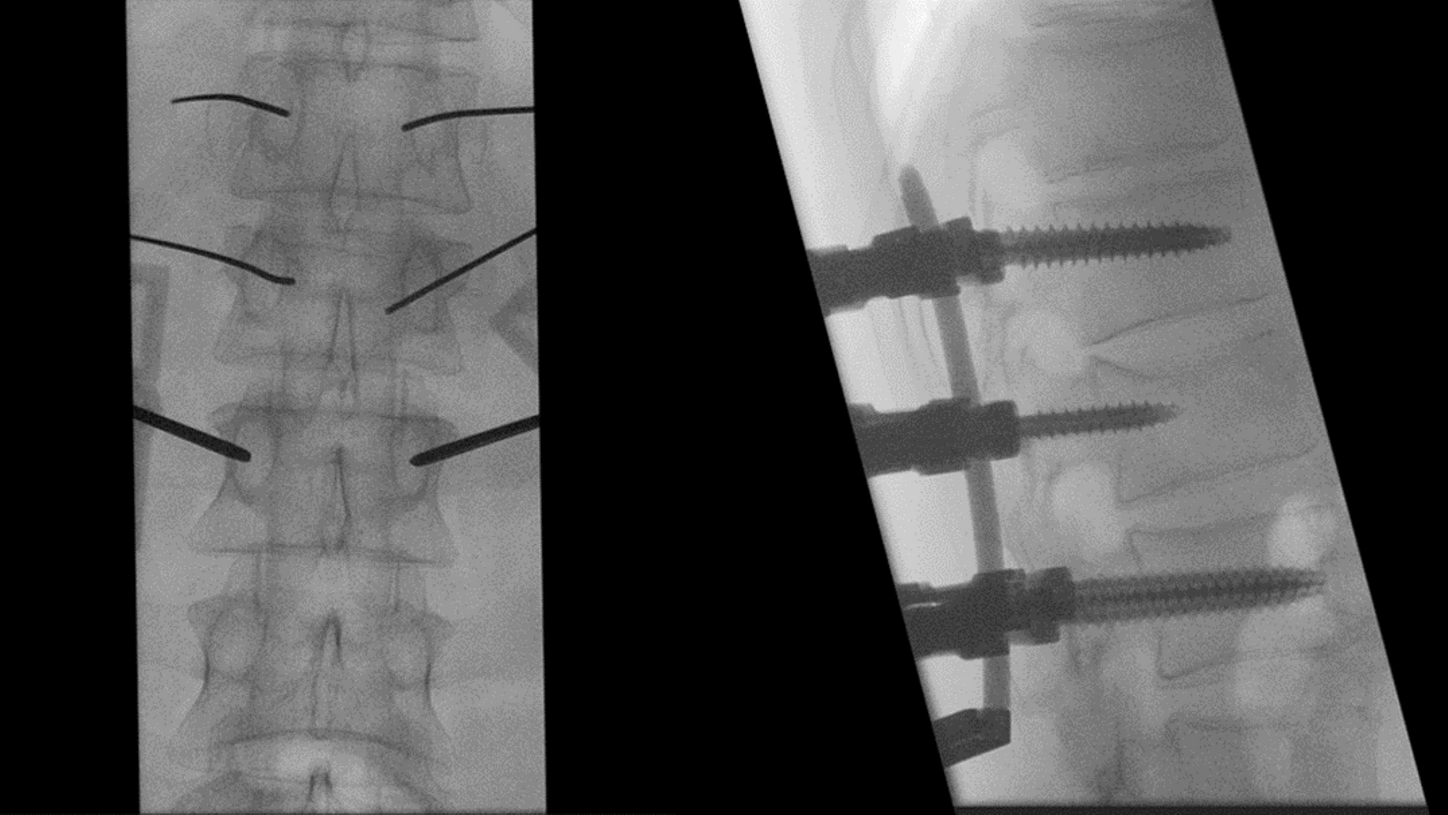

CIARTIC Move already has proven its benefits  in a preclinical study1: The system enabled significant time savings for all three anatomical regions included in the study (pelvis, spine, distal radius).

White paper on how spine surgery benefits from the self-driving mobile 3D C-arm CIARTIC Move.

Benefits for spine surgery